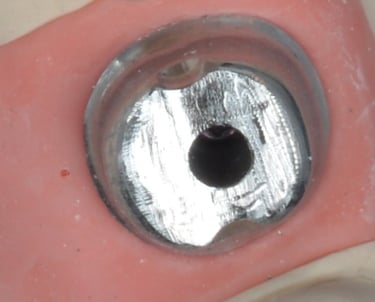

Die individuellen Abutments von Goodent werden auf Basis intraoraler Scans oder präziser Modelldaten konstruiert und exakt an die Anatomie, die Implantatangulation sowie den prothetischen Behandlungsplan des jeweiligen Patienten angepasst.

✔ Individualisiertes Emergenzprofil

✔ Korrektur der Implantatangulation

✔ Stabiles periimplantäres Weichgewebe

ei Goodent werden individuelle Abutments digital auf Basis intraoraler Scans und CBCT-Daten entworfen und aus Titan oder Zirkoniumdioxid präzise gefräst.

Sie sind mit allen gängigen Implantatplattformen kompatibel und als verschraubte oder zementierte Lösungen verfügbar.

Durch die exakte Anpassung an Weichgewebe und prothetischen Plan sorgen unsere Abutments für einen optimalen Kronensitz, verbesserte Ästhetik und gesundes periimplantäres Gewebe – für Vertrauen vom Scan bis zum Lächeln.